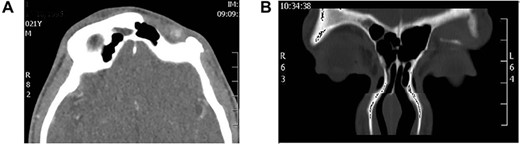

Case 3: subdural empyema

Young girl presented with unresolving sinusitis associated with fever, headache, vomiting and drowsiness. Diagnosed on CT brain as a case of SDE (Fig. 3A and B) as a complication of frontal sinusitis. The patient was managed by systemic intravenous antibiotic. Endoscopic frontal sinusotomy and frontal mini craniotomy to drain the empyema by the neurosurgery team. The patient recovered well with no complications as shown in follow-up CT scan (Figure 3C).

(A) axial CT brain with subdural empyema, (B) sagittal CT scan with subdural empyema and (C) post drainage CT brain with complete resolution of subdural empyema.